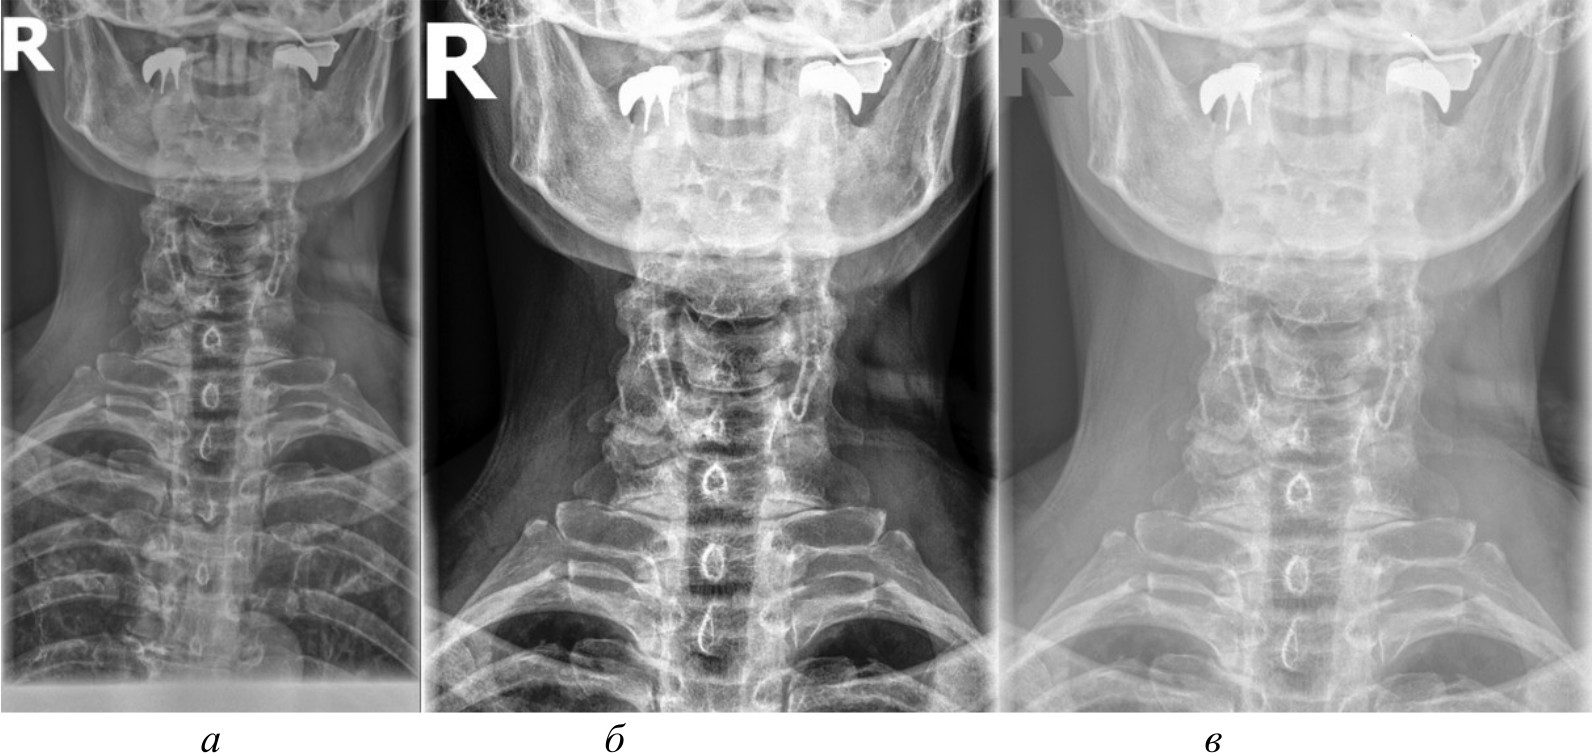

На рис. 4, 5 и 6 представлены результаты работы детектора Харриса, алгоритма Shi-Tomasi и SIFT при различных методах предварительной обработки изображений.

Рис. 4. Результаты работы детектора Harris на изображении, полученном при помощи специализированного программного обеспечения (а); результаты работы детектора Harris при методе адаптивной эквализации гистограммы (б); результаты работы детектора Harris при методе стандартной эквализации гистограммы (в); результаты работы детектора Harris при методе гамма-коррекции (г)

Рис. 5. Результаты работы алгоритма Shi-Tomasi на изображении, полученном при помощи специализированного программного обеспечения (а); результаты работы алгоритма Shi-Tomasi при методе базового отображения в Python (б); результаты работы алгоритма Shi-Tomasi при методе базового отображения Python с применением медианного фильтра (в); результаты работы алгоритма Shi-Tomasi при методе адаптивной эквализации гистограммы (г); результаты работы алгоритма Shi-Tomasi при методе стандартной эквализации гистограммы (д); результаты работы алгоритма Shi-Tomasi при методе гамма-коррекции (е)

Рис. 6. Результаты работы алгоритма SIFT на изображении, полученном при помощи специализированного программного обеспечения (а); результаты работы алгоритма SIFT при методе адаптивной эквализации гистограммы (б); результаты работы алгоритма SIFT при методе стандартной эквализации гистограммы (в)